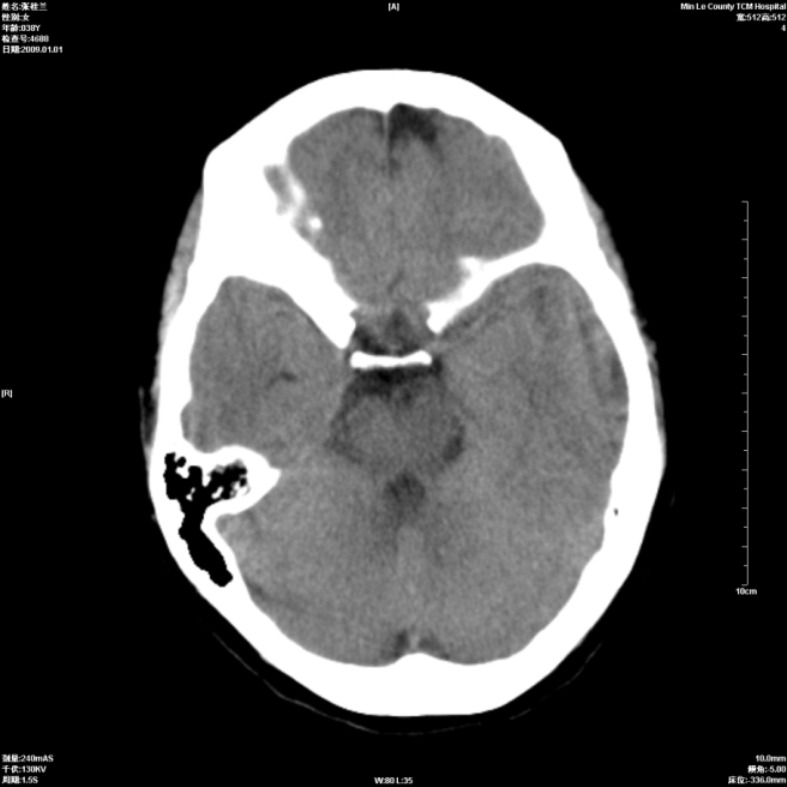

以下是引用hhcckk在2009-1-1 15:56:00的发言:[br]癫痫的原因一般与四种因素有关:[br] 1.遗传因素在一些有癫痫病史或有先天性中枢神经系统或心脏畸形的病人家族中容易出现癫痫;[br] 2.脑损害与脑损伤在胚胎发育中受到病毒感染放射线照射或其它原因引起的胚胎发育不良可以引起癫痫;胎儿生产过程中产伤也是引起癫痫的一个主要原因;颅脑外伤也可引起癫痫;[br] 3.颅脑其它疾病脑肿瘤脑血管病颅内感染等;[br] 4.环境因素;男性病人较女性病人稍多农村发病率高于城市另外发热精神刺激等也是癫痫发生的诱因。[br][br]此病例在额叶有片状低密度灶,无明显占位与负占位效应,结合癫痫的常见原因考虑[br]1、外伤后软化灶,包括产伤,可以结合病史鉴别[br]2、血管畸形的窃血现象形成的萎缩?

以下是引用xulianj在2009-1-1 16:09:00的发言:[br]支持:蛛网膜粒囊肿!